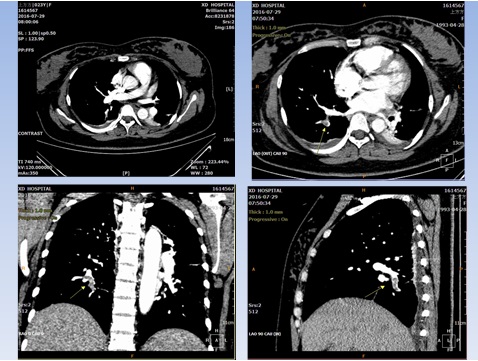

術(shù)后36小時(shí),正值凌晨五點(diǎn),患者突然出現(xiàn)胸悶、心慌氣短,不能平臥的緊急狀況,值班醫(yī)生考慮“心功能不全、肺栓塞?”,急請(qǐng)相關(guān)科室會(huì)診進(jìn)行搶救治療。產(chǎn)科賈小文主任、李宏副主任醫(yī)師也趕到搶救,再次組織科室進(jìn)行疑難危重病例討論,結(jié)合肺動(dòng)脈造影考慮患者發(fā)生了剖宮產(chǎn)術(shù)后肺動(dòng)脈栓塞。肺栓塞是臨床上危急重癥,發(fā)病急,若不得到積極治療,死亡率可高達(dá)20%~30%。剖宮產(chǎn)術(shù)后肺栓塞發(fā)病隱匿,病情兇險(xiǎn)、復(fù)雜,漏診率高。產(chǎn)科醫(yī)護(hù)通過(guò)對(duì)患者的細(xì)致觀察和對(duì)臨床危急重癥的警覺(jué),快速明確病情,經(jīng)多學(xué)科協(xié)助搶救,患者再次脫離生命危險(xiǎn),轉(zhuǎn)入重癥科,給予抗炎、抗凝、活血、改善循環(huán)、強(qiáng)心等治療,術(shù)后20天患者痊愈出院。

肺動(dòng)脈造影